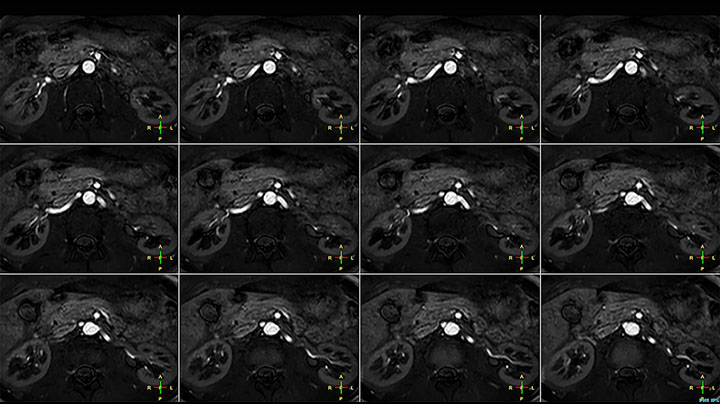

Imaging the renal arteries without contrast agent on Prodiva 1.5T.

Although the area between the neck and the top of the lung is one of the most difficult areas for MRI, Prodiva 1.5T images show good quality in this 56-year-old male with Pancoast tumor on the right. mDIXON TFE images shows excellent fat suppression in the neck area and the DWI shows almost no distortion.